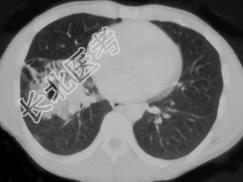

- 单项选择题男,42岁, 高热,寒战, 咳嗽,胸痛1周左右, CT检查如图,选择最可能的诊断 ( )

A、肺结核

B、肺癌

C、肺囊肿

D、肺脓肿

E、肺转移瘤